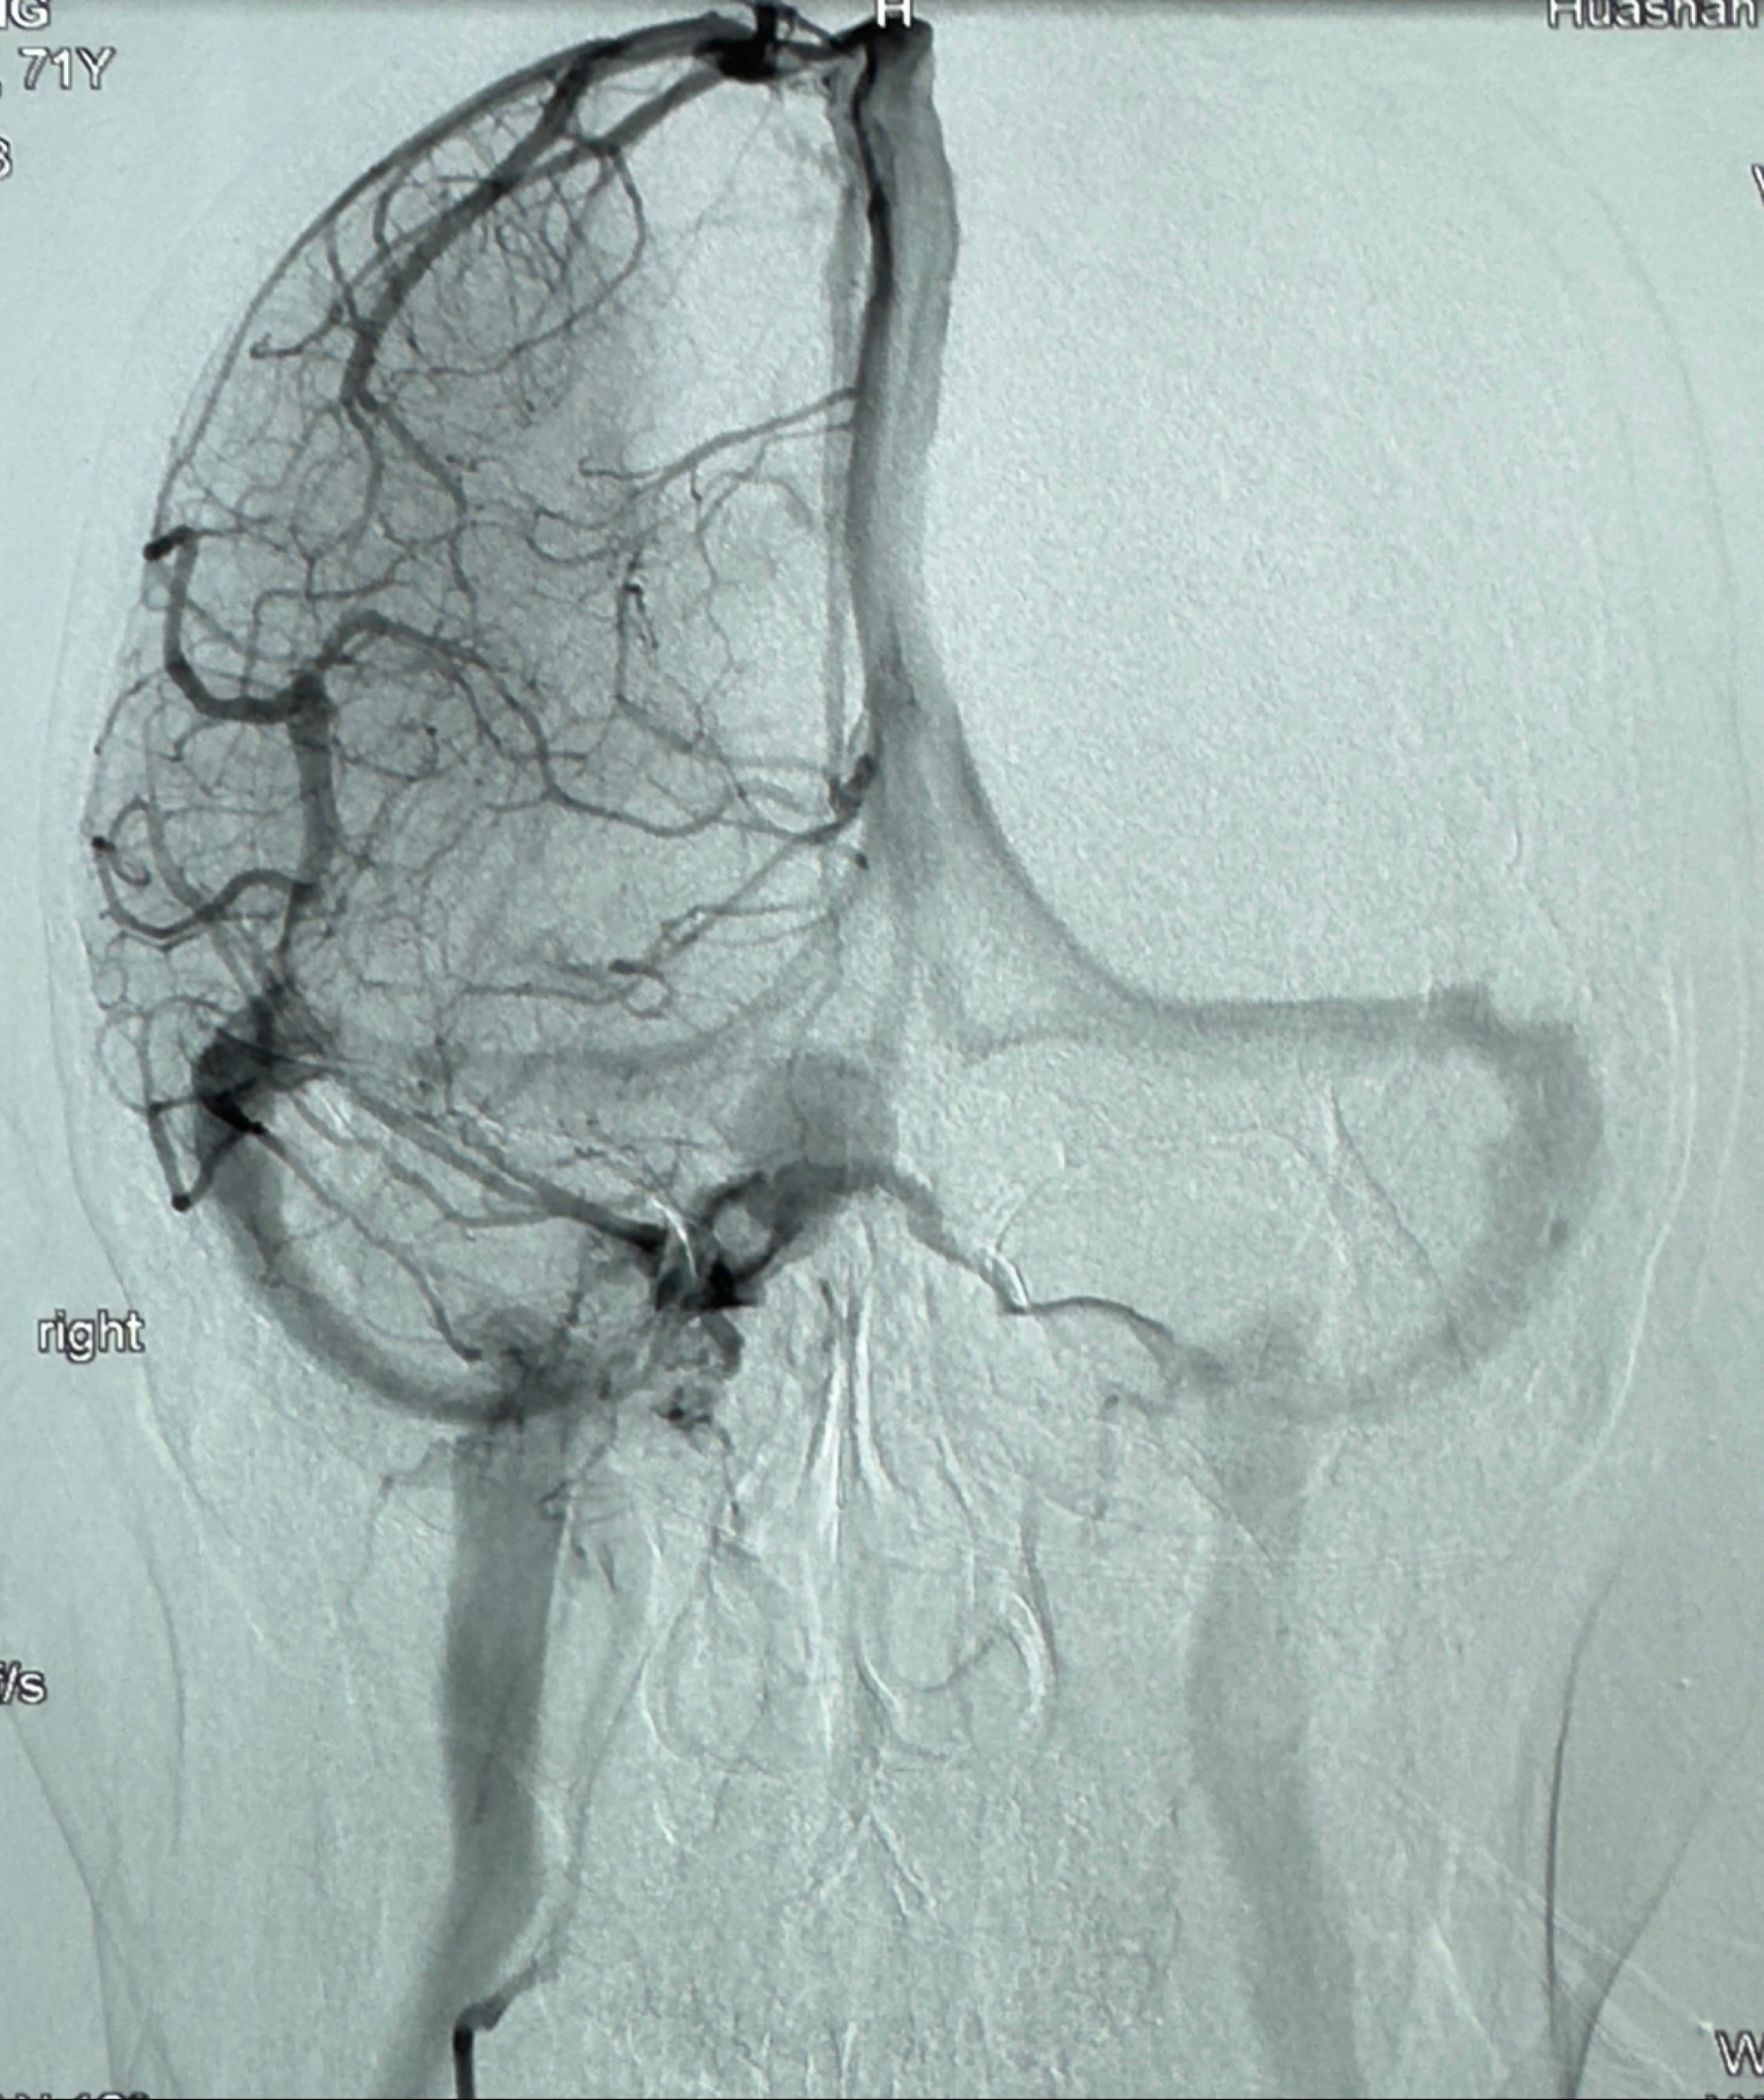

2023-12-27术后第十天复查DSA

支架贴壁佳,但可见射流,咋办?

2024-01-08全麻下再行植入密网支架一枚

Tubridge 4.5-35mm

支架植入顺利,贴壁佳,支架内血流通畅,动脉瘤内血液滞留明显